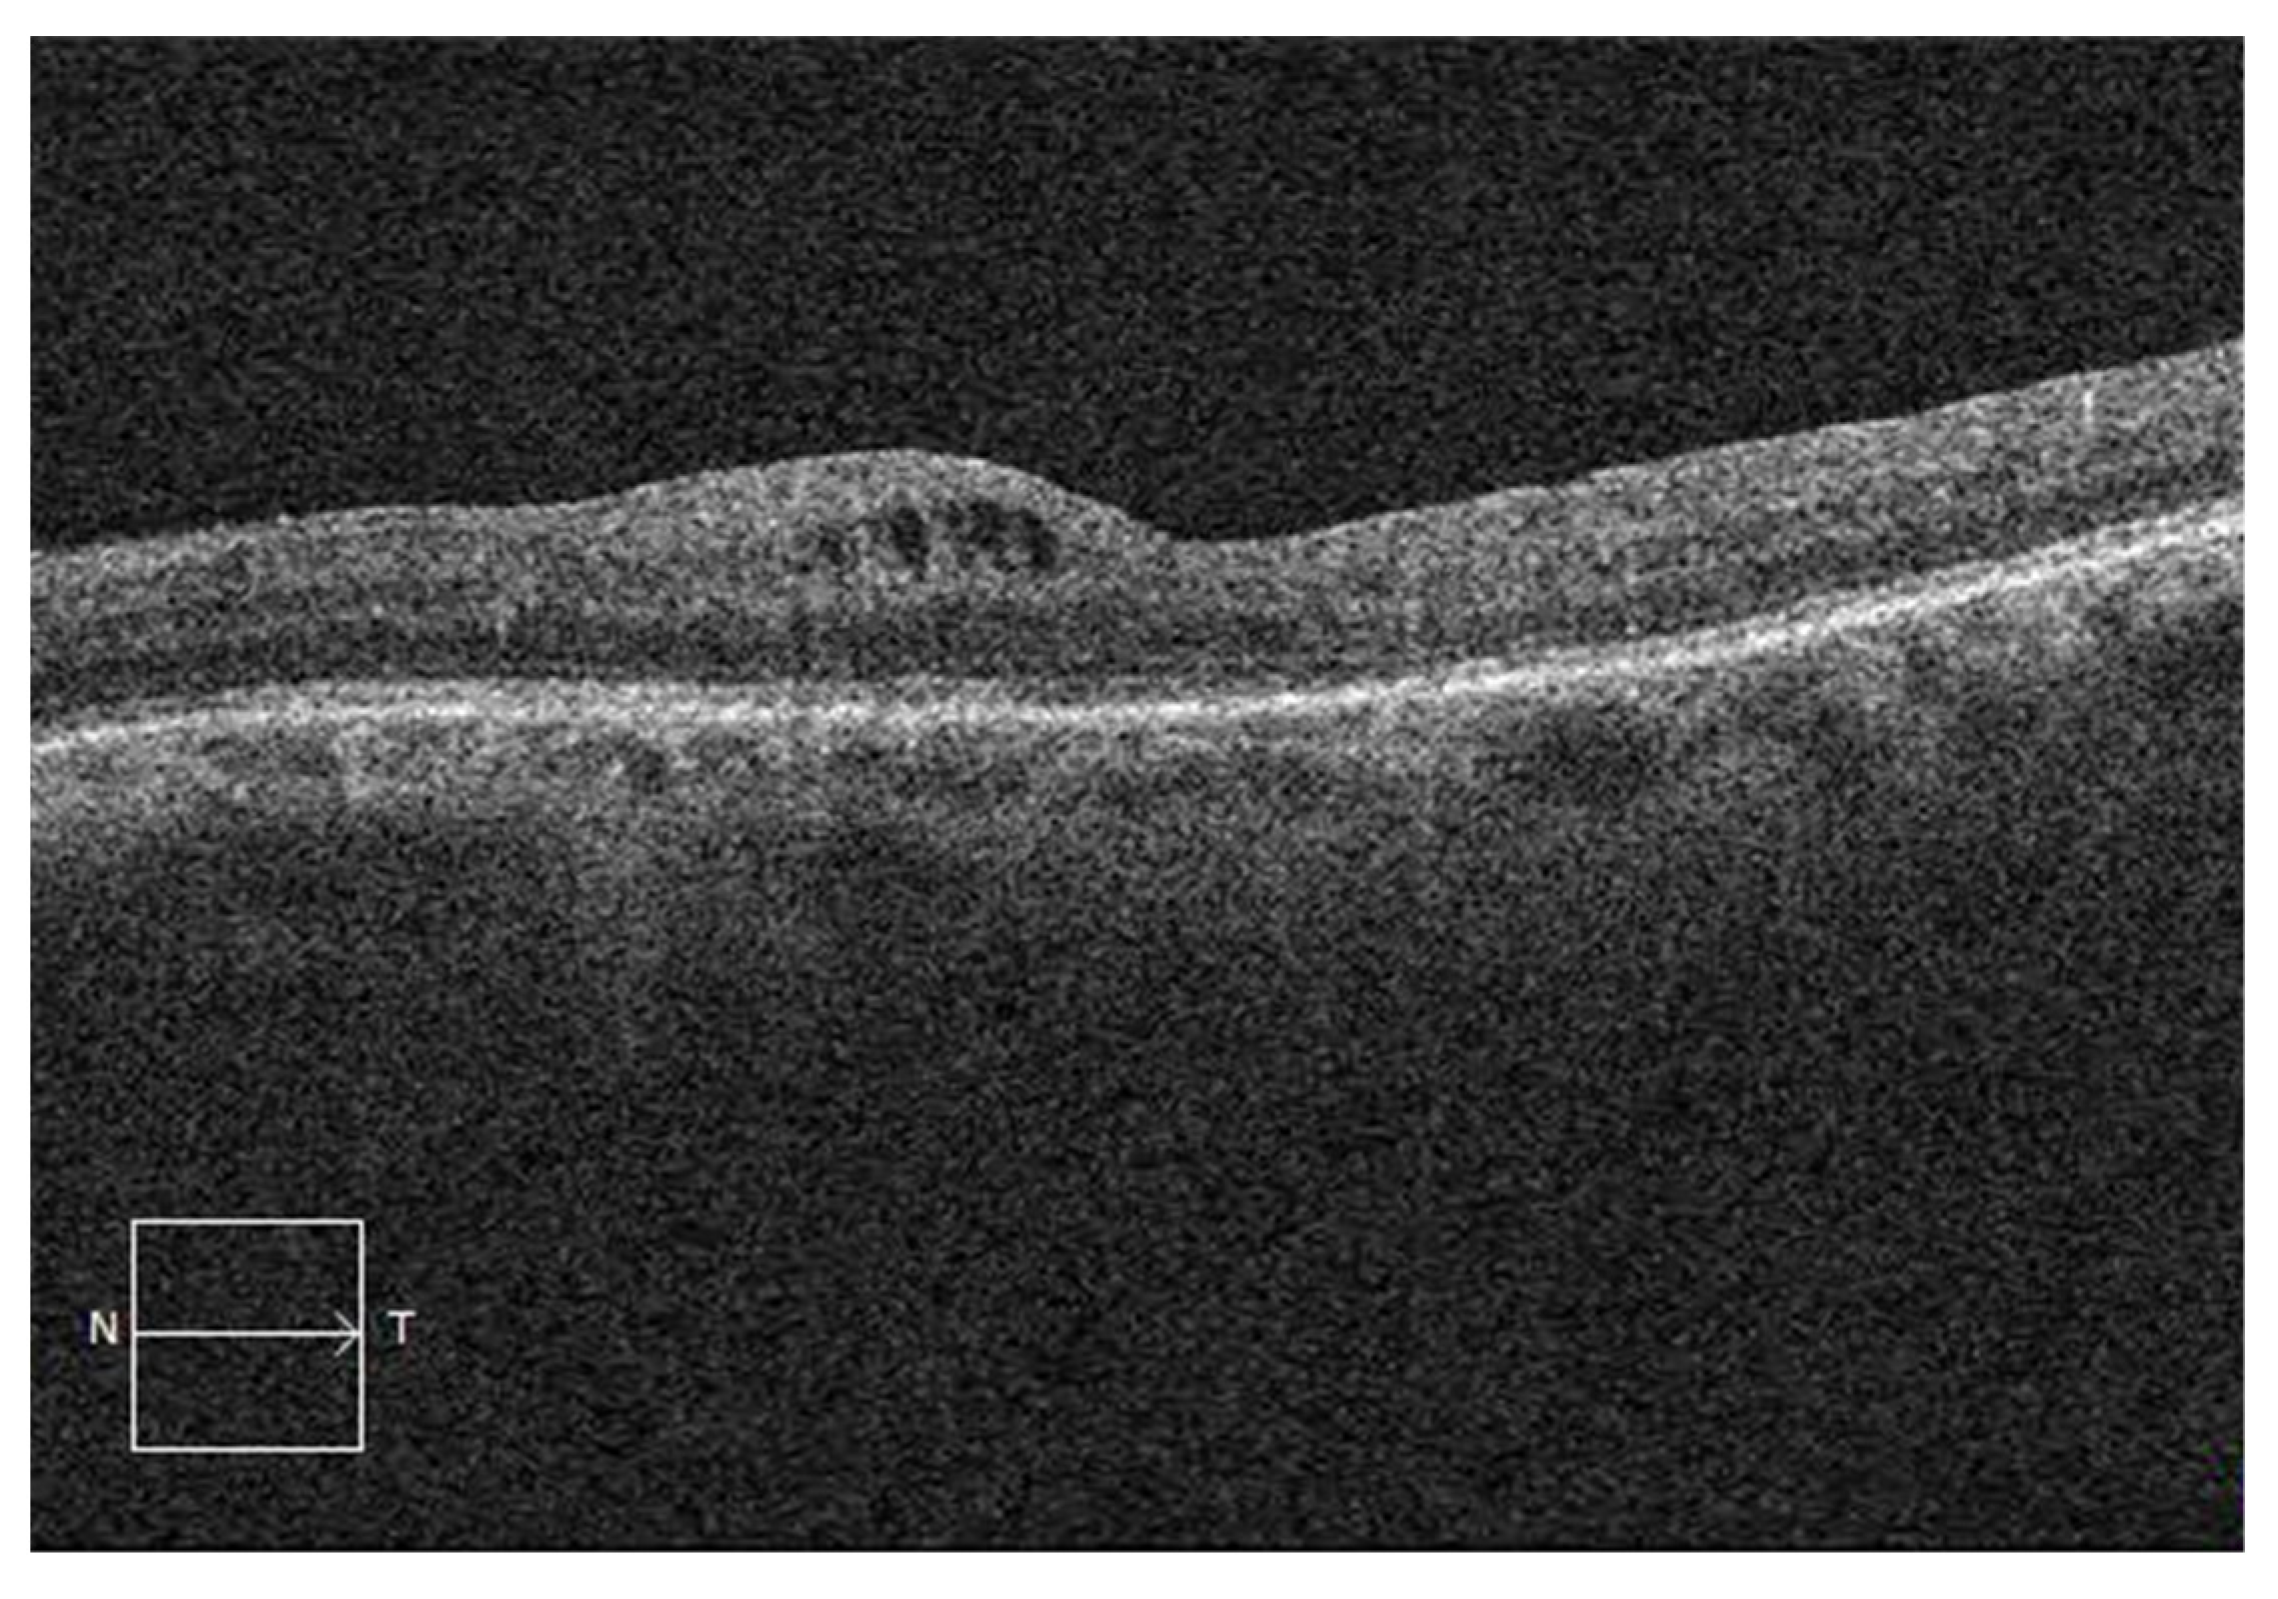

3.4. SD-OCT Characteristics of Postoperative CME

| tCME (n = 56) | cCME (n = 105) | OR * | 95% CI | p Value | |

| Outer retinal layer alteration | 38 (67.9%) | 86 (81.9%) | 2.14 | 1.01–4.56 | 0.046 |

| Macular cysts localization | |||||

| IRL | 41 (73.2%) | 35 (33.3%) | |||

| ORL | 1 (1.8%) | 4 (3.8%) | 4.69 | 0.66–94.0 | 0.18 |

| IRL and ORL | 12 (21.4%) | 66 (62.9%) | 6.44 | 3.08–14.3 | <0.001 |

| Subretinal fluid | 3 (5.4%) | 12 (11.4%) | 2.28 | 0.69–10.3 | 0.22 |